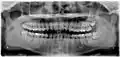

Рентгеновский снимок ретинированного нижнего правого зуба мудрости с горизонтальной ориентацией

Дистоугольно ретинированы верхний левый (изображение справа) и верхний правый (изображение слева) зубы мудрости. Левый нижний зуб мудрости ретинирован горизонтально. Нижний правый зуб мудрости вертикально ретинирован.